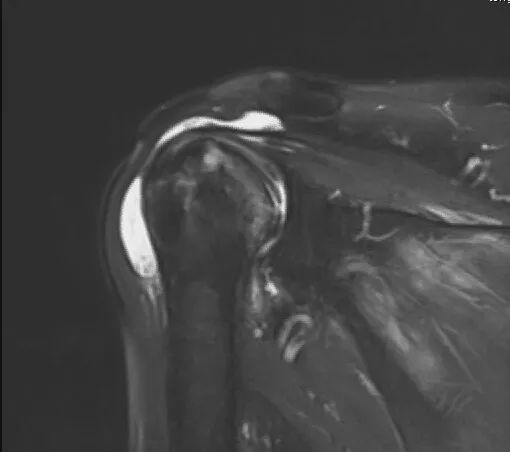

近日,我院关节运动一病区成功完成反式人工全肩关节置换术(reverse total shoulder arthroplasty, RTSA),帮助肩痛患者重获肩关节功能。